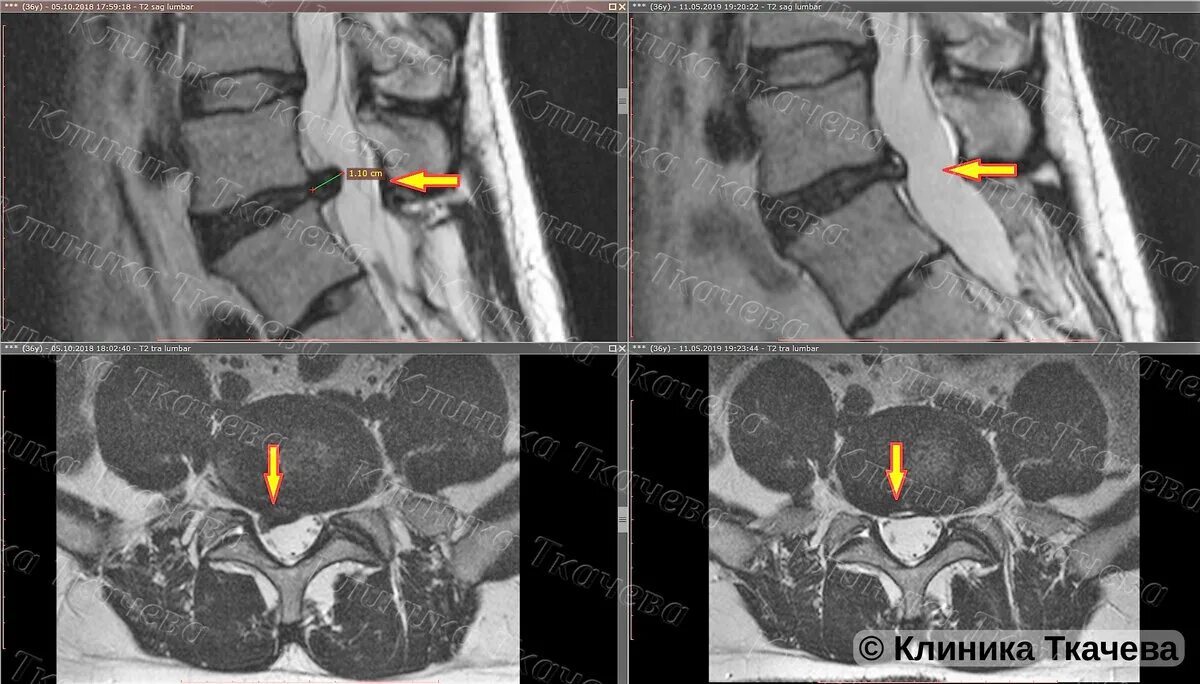

Что такое резорбция грыжи позвоночника